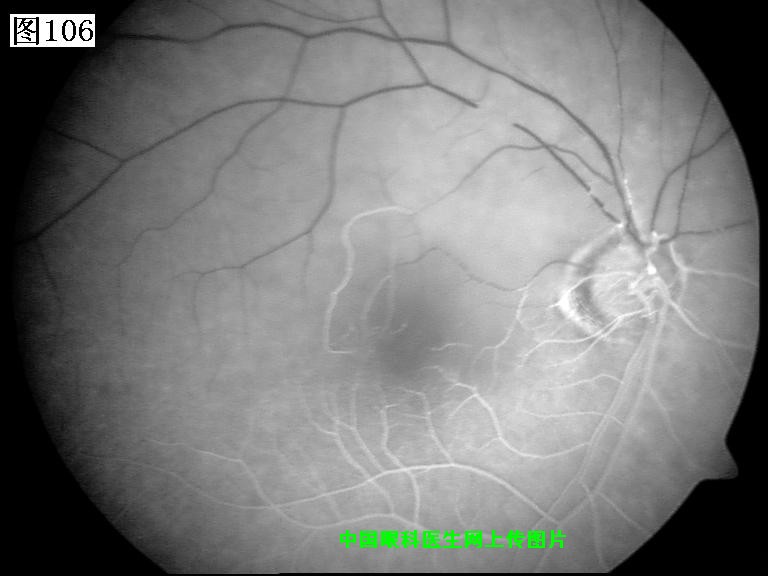

105 106 107 108